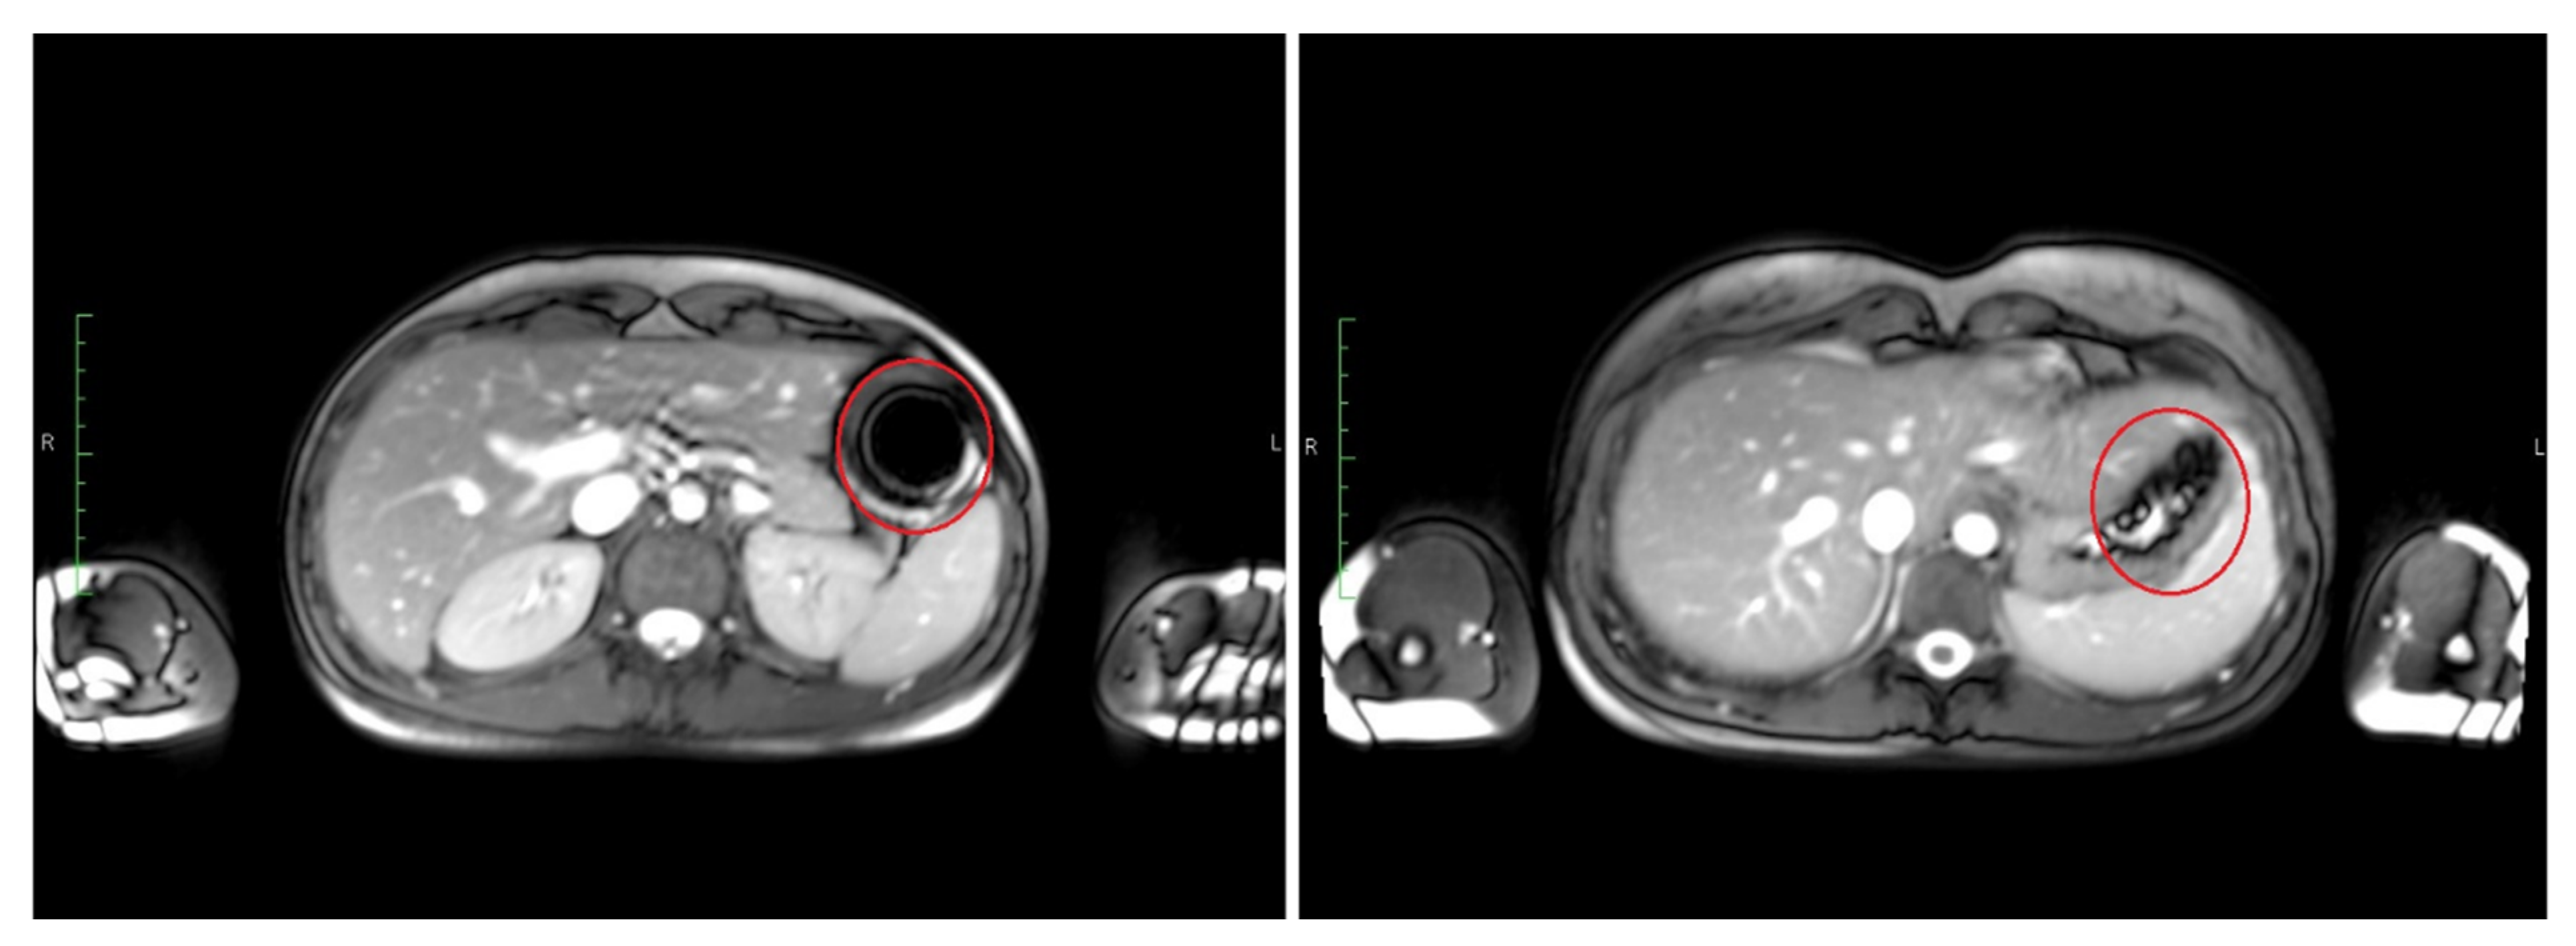

The time point of detected disintegration for the inner capsule in turn (detected in TRUFI sequence) was defined as the time of spreading of the characteristically shaped susceptibility artifact in the GI tract or visible sedimentation of the iron oxide within the stomach. Exemplary images of such an intact and disintegrated artifact are shown in Figure 3. The section of the GI tract in which the susceptibility artifact or the corresponding iron oxide particles were located at the time of the determined disintegration was assessed as the disintegration site of the inner capsule.

Figure 3.

Transversal images of T2*/T1 weighted TRUFI with an intact susceptibility artifact of iron oxide at 10 min (left) and the same artifact after disintegration at 30 min (right).